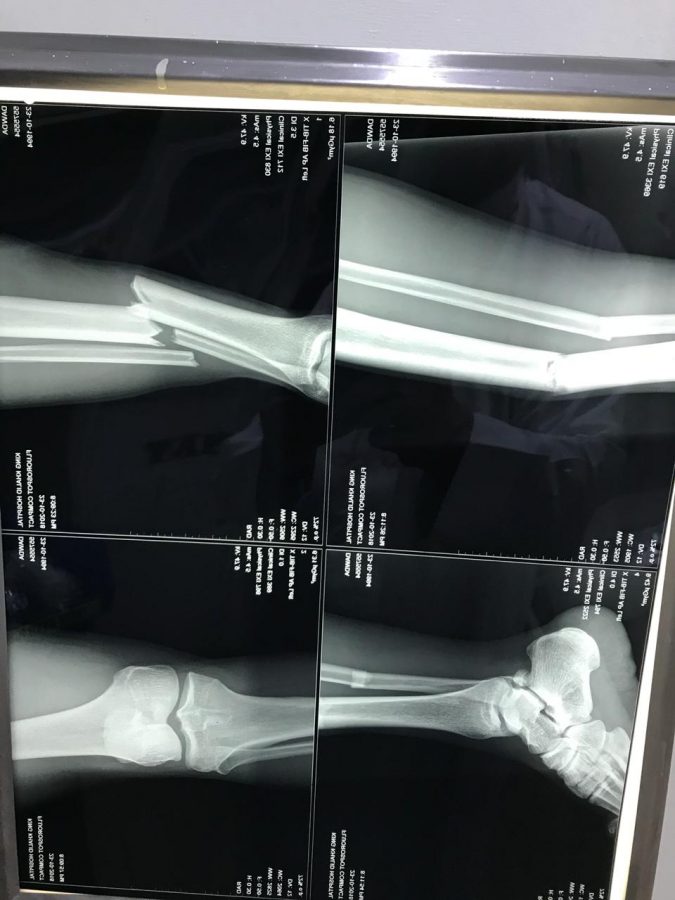

تعرض لاعب نادي أبها الرياضي المهاجم الغيني (داودكمارا”الى كسر مضاعف بالساق وذلك بعد إشتراكه مع حارس المجزل خلال المباراة الدورية بين الفريقين يوم الثلاثاء المنصرم تم نقله على إثرها لمستشفى الحياة الوطني وستجرى له يوم غد الخميس عملية جراحية قد يغيب بسببها عن الملاعب لمدة تزيد على أربعة أشهر وقد حصلت صحيفة “عسير الالكترونية “على صور للاعب أثناء نقله للمستشفى وكذلك على الأشعة التشخيصية والتي أظهرت مدى الإصابة التي تعرض لها اللاعب الجدير بالذكر أن النادي الأبهاوي أستطاع أن يعتلى سلم دوري الأمير محمدبن سلمان لإندية الدرجة الأولى برصيد 19نقطة وإستطاع خطف الأضواء والإنفراد بصدارة الدوري وذلك رغم الإمكانيات القليلة والمحدودة وعدم وجود منشأة رياضية متكاملة الإ أنه استطاع كسب الرهان وإعتلاء الصدارة ويتطلع محبو النادي وجماهيره الى مواصلة حصدالنقاط والإبتعاد عن أقرب منافسيه نادي “جدة” في حين سيلعب مباراته القادمه مع فريق الوشم يوم الأربعاء القادم على ملعب نادي ضمك بخميس مشيط.